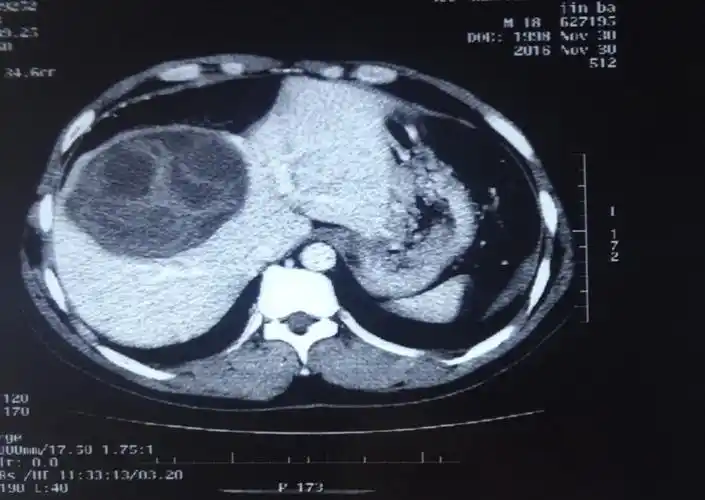

用针做手术--超声引导下穿刺抽吸联合微波消融治疗肝囊型包虫病